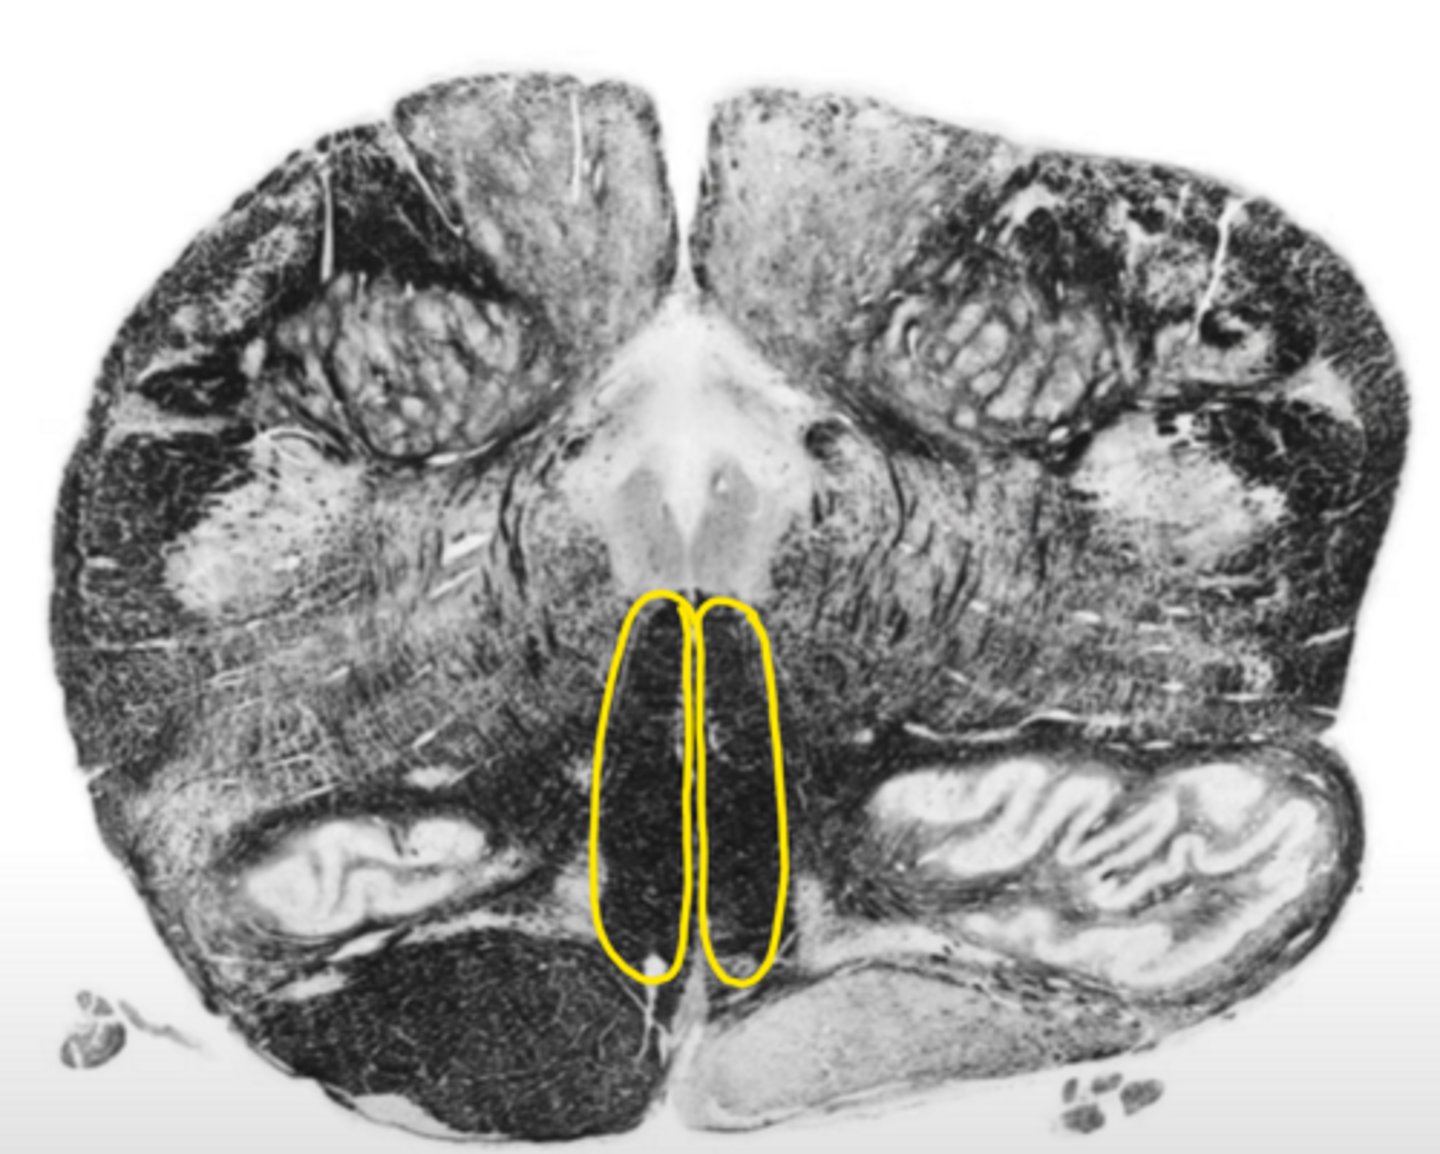

central canal

ID the space